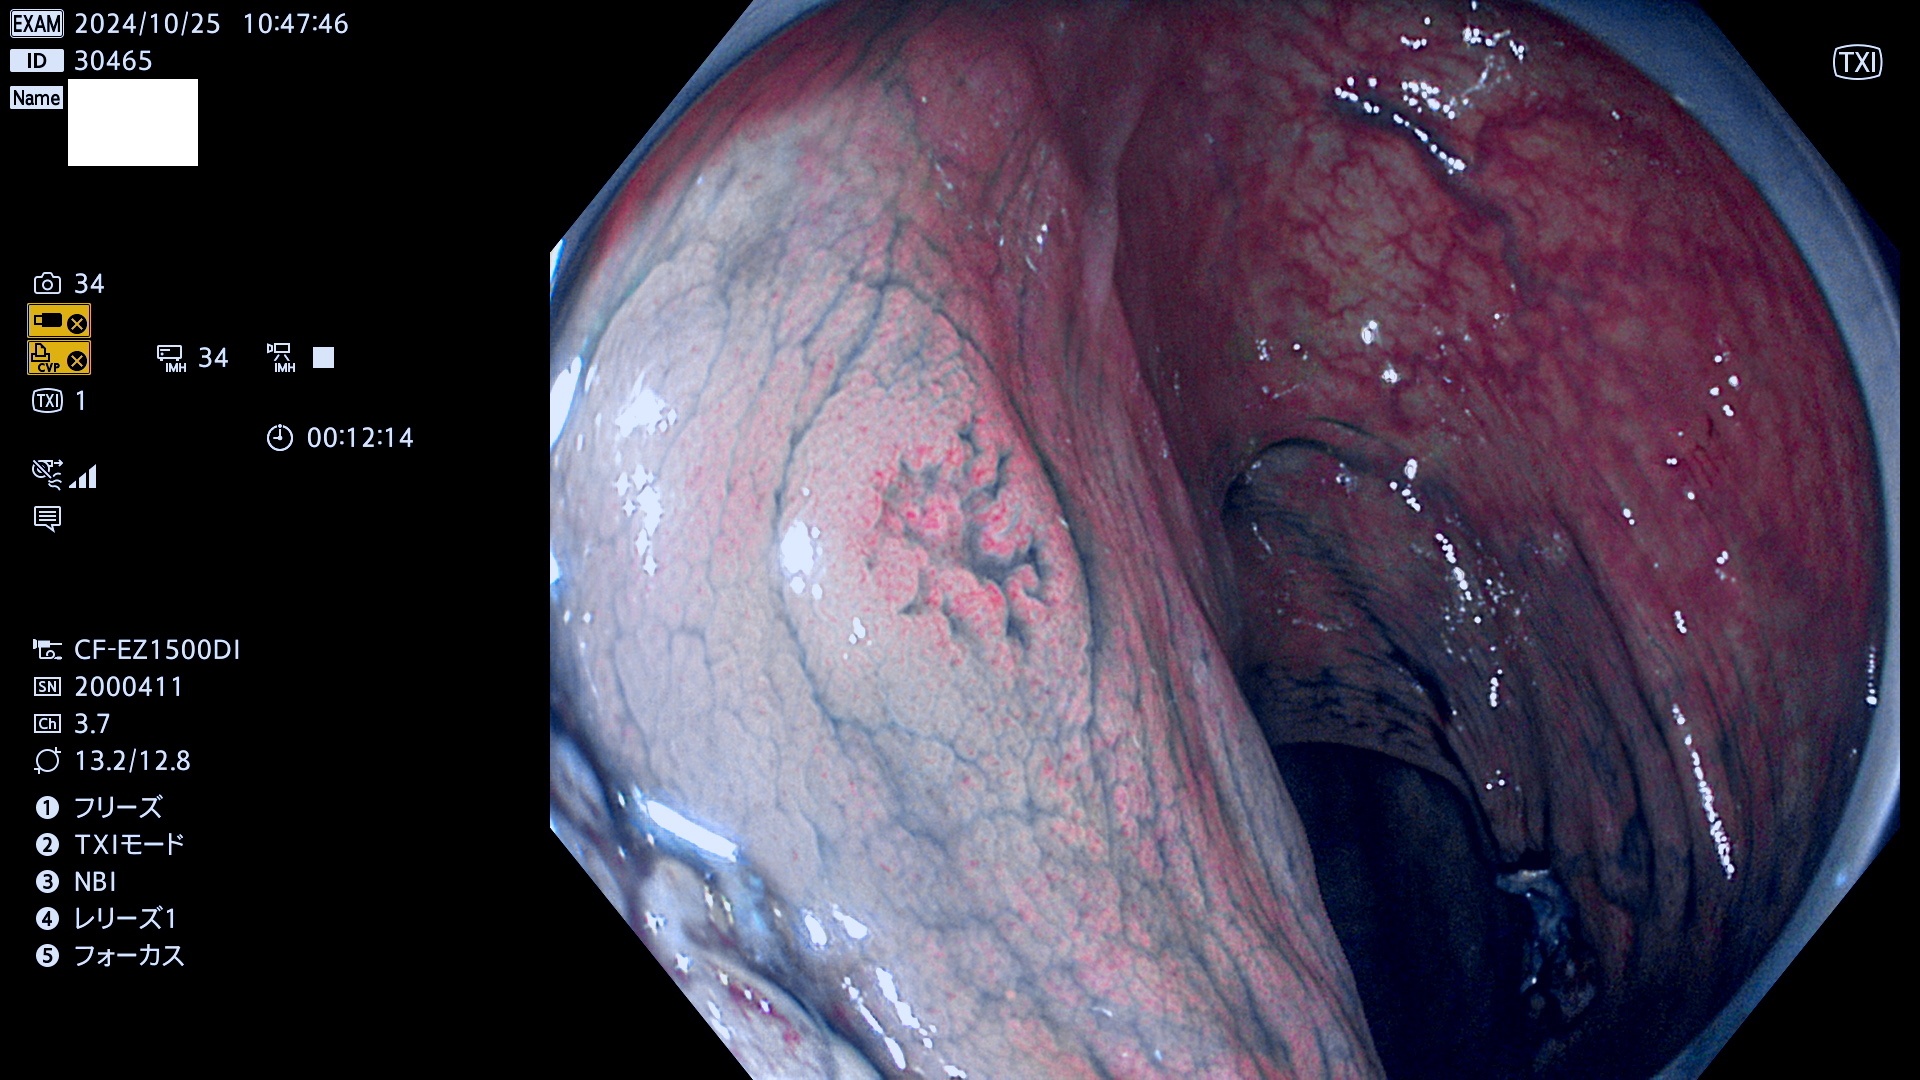

完全に平坦な物をUb、陥凹している物をUcと呼びます。最も発見が難しく危険な病変です。

毎週の検査(木・金・土・日)に発見されたUb、Uc型・腺腫を、その週の日曜の夜にUPし1週間、提示します。

抽出の対象期間 2024年10月24日〜10月27日の4日間(48件の検査)7件 (7/48=15%)